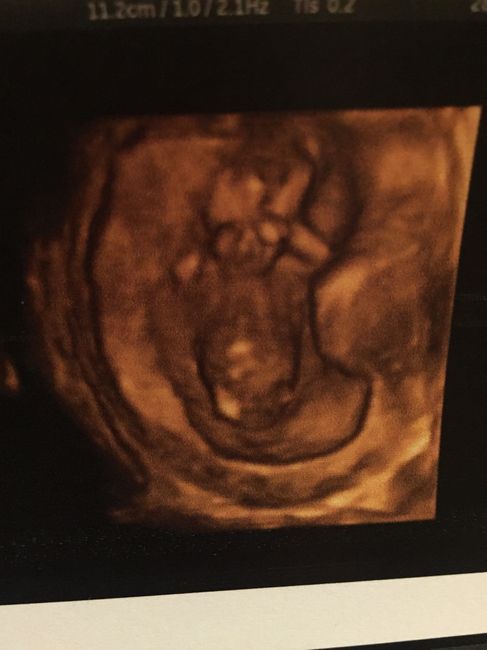

Buongiorno mammineeee come preannuncia il titolo si parla di bitest e sesso del fagiolino/a. Ieri a 11+4 io e mio marito siamo andati dalla gine per il bitest, il risultato è stato eccellente e questa è la cosa più importante, ora attendiamo comunque...